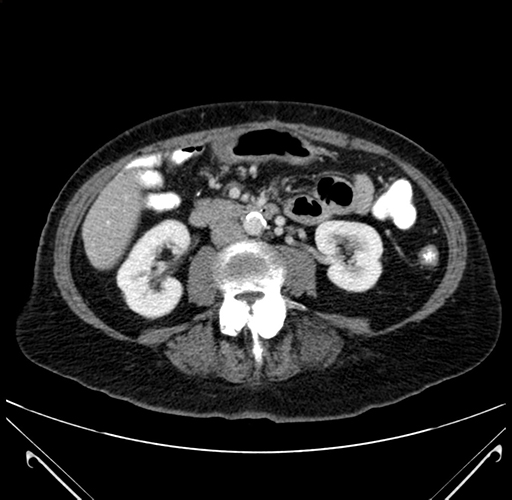

Pre-Chemo: Axial Venous

Axial Venous